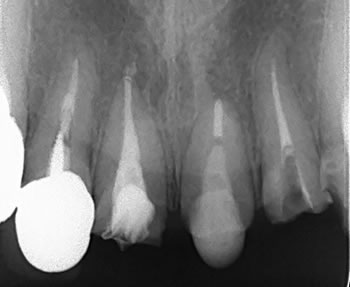

だいぶ伸びてきました!!!

これはやり過ぎると歯根自体が短くなりますので、

ほどほどに、、、

とりあえずファイバーポストを入れて、この歯は完了です!

今度はもう一つ隣の歯の根管治療を行い、、、

仮歯は必要でし、固定源もいるので地道に1本ずつの作業、、、 |

これにフックを付けて引き出します~!

何でこんな事をするの???と疑問に思われるかもですが、

骨に生えている歯根には歯肉が結合するだけの「のりしろ」が必要なのです!

歯肉の上皮と結合組織で最低限2mm以上必要です!

骨の近く(歯肉のなかまで)まで折れてしまった歯牙には、おそらくこの「のりしろ」になるだけの根面が無いのです!

そこで骨の中から新鮮な根を引き上げて使おうという作戦です!

まさに根こそぎ引き出す作戦です!!! |